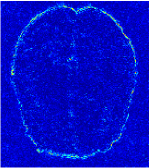

In general supervised learning, training data need to be in the same or similar distribution, heterogeneous data exhibits different structure variations of features which hinders CNNs to extract features efficiently. In our experiments, raw measurements sampled from different ratios of compressed sensing display different levels of incompleteness, these undersampled measurements do not fall in the same distribution but they are related. Different sampling masks are shown at the bottom of Figure 1 and 2 may have complemented sampled points, in the sense that some of the points which sampling ratio mask does not sample have been captured by other masks. In our experiment, different sampling masks provide their own information from their sampled points so that four reconstruction tasks help each other to achieve an efficient performance. Therefore, it explains the reason that Meta-learning is still superior to conventional learning when the sampling ratio is large.

Qualitative comparison between conventional and Meta-learning methods are shown in Figure 1 and 3, which display the reconstructed MR images of the same slice for T1 and T2 respectively, we label the zoomed-in details of HGG in the red boxes. We observe the evidence that conventional learning is more blurry and lost sharp edges, especially in lower CS ratios. From the point-wise error map, we find meta-learning has the ability to reduce noises especially in some detailed and complicated regions comparing to conventional learning.